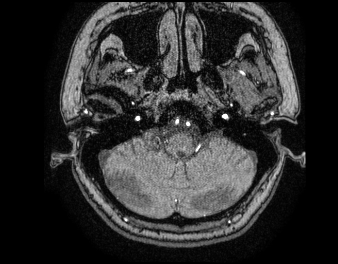

Mri 뇌 사진인데 저 하얀 점 뭐에요?

Mri 찍엇는데요 영상을 받아왓어요 근데 저 하얀 점처럼 찍혀잇는건 뭔가요?? 혈관인가요? 넘 쌩뚱맞게 찍혀잇어서요. 아하에서 궁금증 풀어주셔서 너무좋네요

• 1번 째 사진

흰 점들은 혈관이 보이는 것입니다. 단면으로 잘라서 보는 영상이니 둥글게 보입니다.

하얀 점처럼 찍혀있는 부분이 크게 중간부분에 두개 그 양 옆으로 두개가 더있어서 4개가 잘 보이는데요.

내경동맥과 척추동맥으로 보이고 정상입니다.